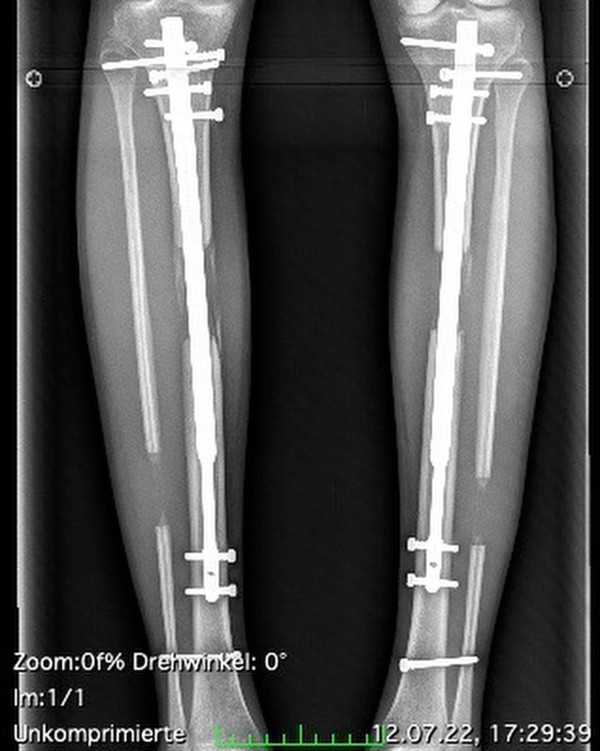

Theresia Fischer事後回想起這段增高過程直言是「惡夢般痛苦」,「我的脛骨被打斷,小腿肌肉被撕裂,在裡面還安裝一個可伸縮的裝置,每次使用裝置時都可以聽到『咔噠咔噠』的聲音」,她更指出,手術後還得承受即使吃止痛藥也不能忍受的劇痛。